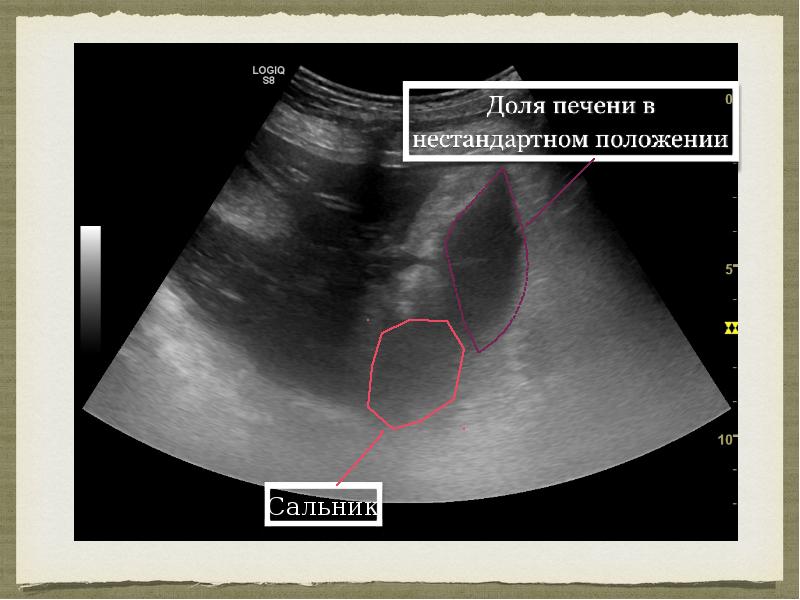

- 8. Ультразвуковое исследование Описание: …в области ворот печени справа доля печени (сосцевидная?